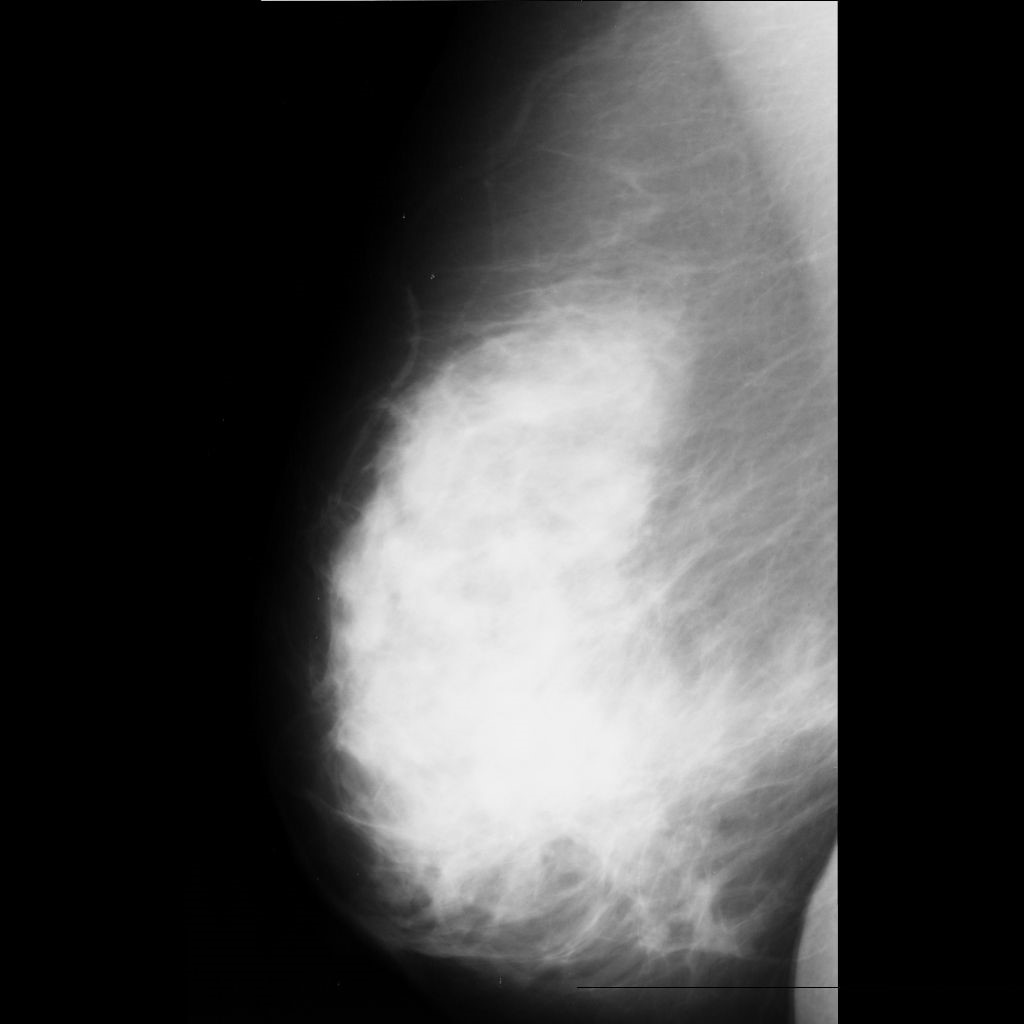

malignant